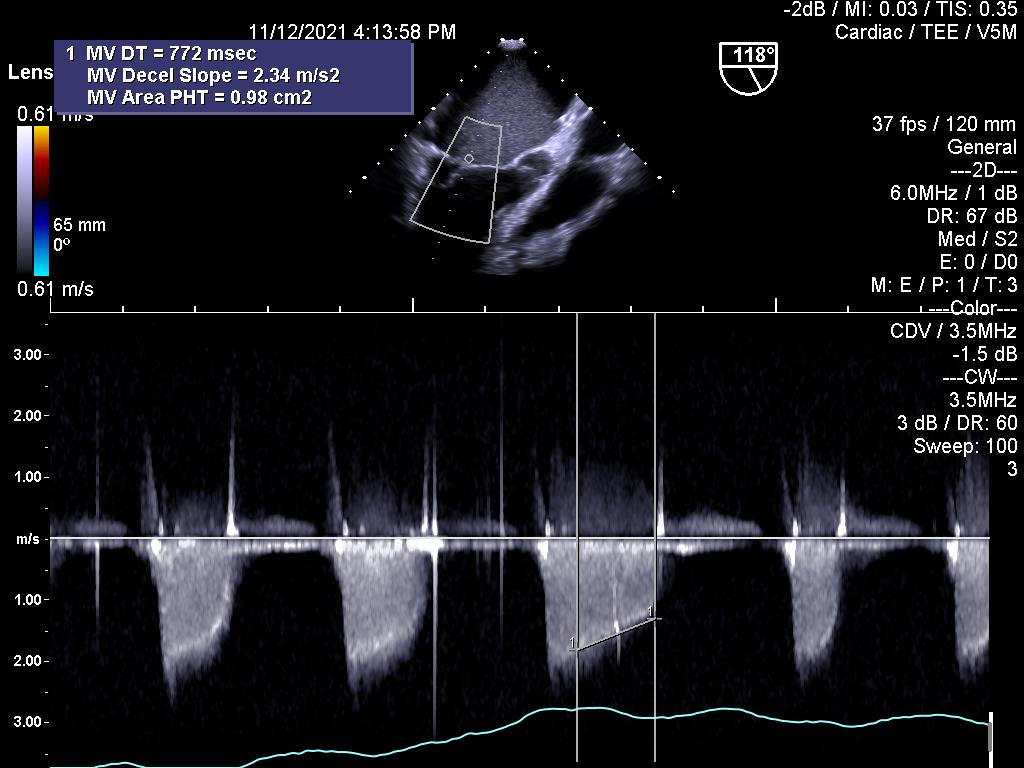

1.Huyết khối gây kẹt van hai lá cơ học:

2.Đánh giá hiệu quả điều trị bằng thuốc tiêu sợi huyết đối với kẹt van cơ học (cùng bệnh nhân ở trên)

7.Dẫn đường hỗ trợ nong van hai lá bằng bóng

Trước nong van:

Sau nong van: